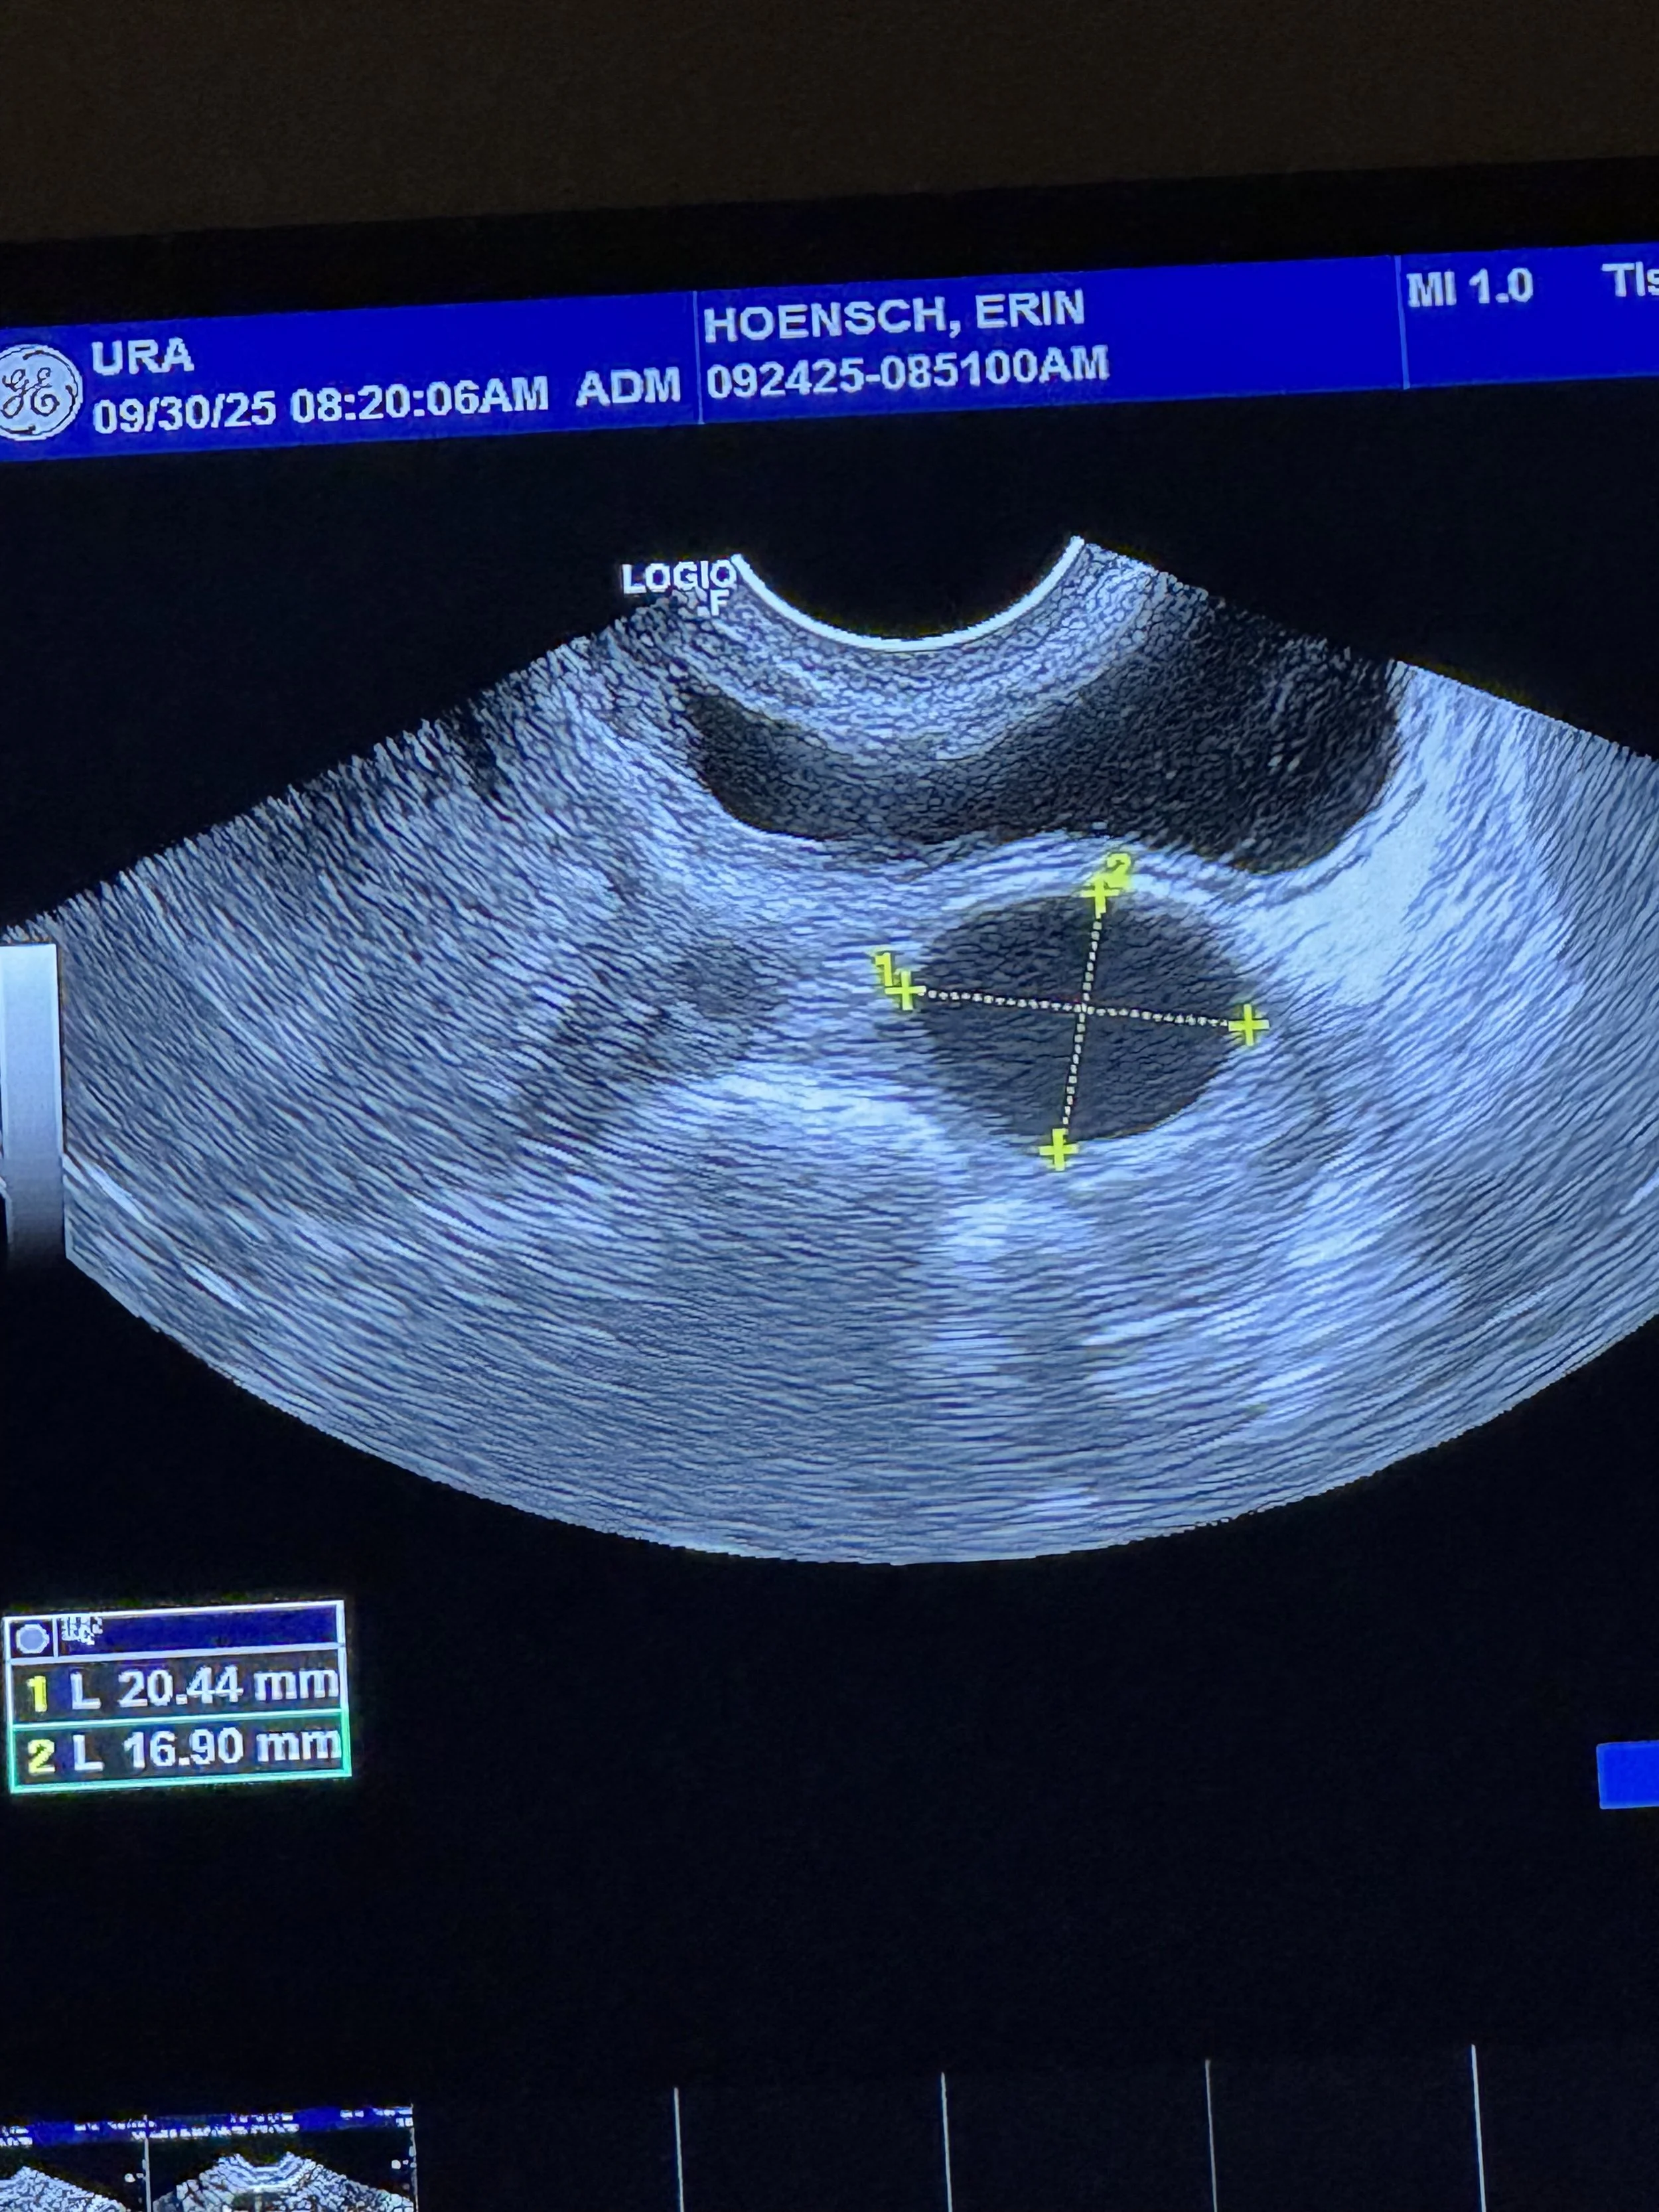

Now, after years of trying naturally, Erin and Kingsley are ready to take the next step: IVF. It is not the path they imagined. But they are not the kind of people who let go of a dream simply because the road got longer.